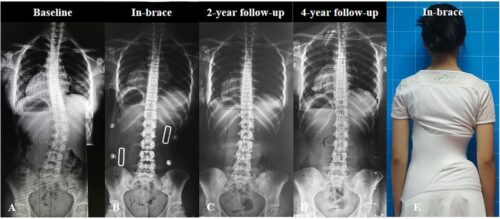

عادةً ما يبدأ التحسن في غضون عدة أشهر من الالتزام المنتظم بحزام اعوجاج العمود الفقري.

ويتم تقييم النتائج بشكل دوري من خلال الأشعة السينية لقياس زاوية الانحناء (زاوية كوب).

إذا أظهرت المتابعة أن الانحناء لم يتفاقم، فهذا يعني أن العلاج بالحزام ناجح، ويستمر حتى اكتمال النمو العظمي.

أما في الحالات التي تستمر فيها الزيادة رغم الالتزام، فقد يوصي الطبيب بخيارات علاجية أخرى.

نجاح الحزام الطبي لعلاج اعوجاج العمود الفقري عند المراهقين لا يعتمد على ارتدائه فقط، بل على تفاصيل دقيقة مثل تصحيح دوران الفقرات الأولى وسرعة هذا التصحيح. متابعة الأهل مع الطبيب، الالتزام بعدد ساعات الارتداء، واستخدام الحزام المصمم خصيصًا لكل طفل، جميعها عوامل تزيد من فعالية العلاج وتمنح الطفل فرصة أفضل لنمو ظهر مستقيم وحياة طبيعية.

التطور الكبير في تصميم الأحزمة الطبية جعل علاج اعوجاج العمود الفقري عند المراهقين أكثر نجاحًا وأقل إزعاجًا. باستخدام تقنيات التصوير الثلاثي الأبعاد والمحاكاة الرقمية، أصبح الحزام أكثر خفة وراحة، ويعطي نتائج أفضل في تصحيح الانحناء والتواء العمود الفقري.